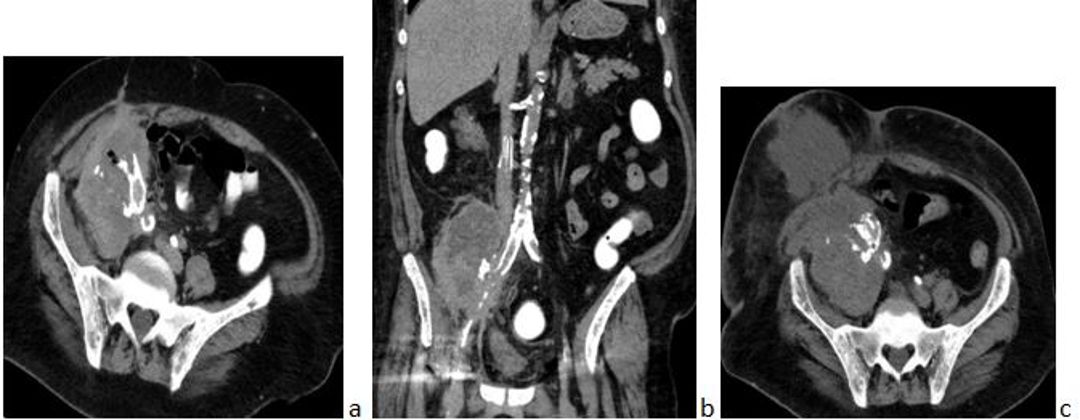

CT imaging revealed thickening of the cecum and ascending colon with surrounding fat stranding but no perforation. The rejected allograft displayed distorted architecture, fluid collections, air pockets in the iliopsoas muscle, and adherence to calcified iliac vessels, raising suspicion of xantho-granulomatous inflammation or malignancy. The patient was admitted to the ICU and treated with intravenous meropenem and vancomycin. Colonoscopy confirmed ischemic colitis. A multidisciplinary team recommended transplant nephrectomy due to the suspicious renal mass.